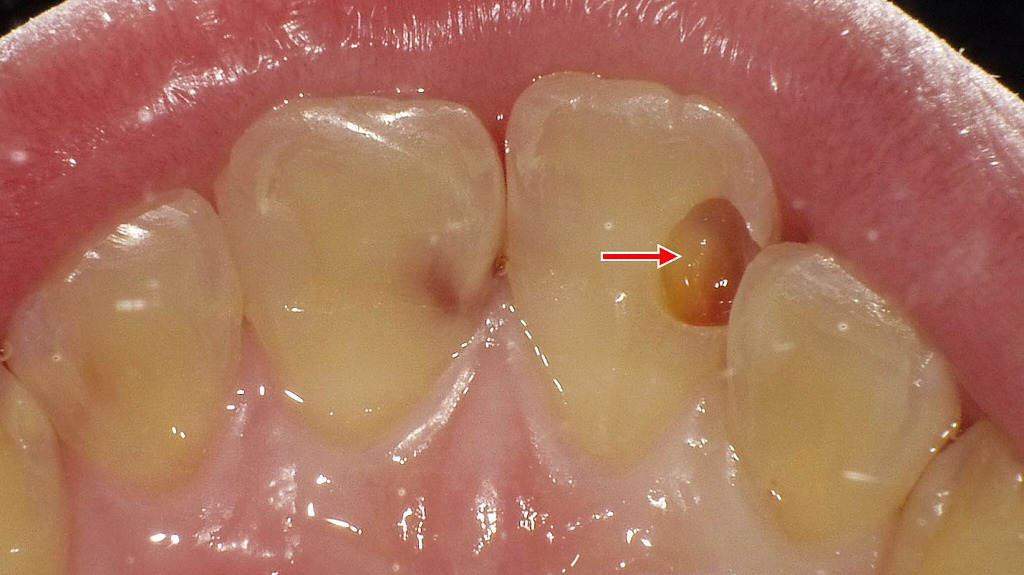

虫歯による穴:症例2

この画像は、下顎の歯列を咬合面(上から)撮影した口腔内写真です。

🔍 解説

赤い矢印で示されているのは右下第2小臼歯(5番)です。

歯の近心側(手前側の面)に、小さな黒い穴が確認されます。これは虫歯(う蝕)によって形成された穴です。

🦷 詳細説明

- 虫歯は歯の表面(エナメル質)から始まり、象牙質へと進行します。

- この段階では穴が浅く、痛みが出にくいこともありますが、放置すると進行して大きくなり、冷たいものがしみたり、神経(歯髄)にまで達するおそれがあります。

- 写真のように、清掃が難しい部位では虫歯が発生しやすくなります。

💡 ポイント

このような小さな虫歯は、早期に発見して治療することで、最小限の削除で済みます。定期的な検診とレントゲン撮影により、見えにくい部位の虫歯も早期発見が可能です。